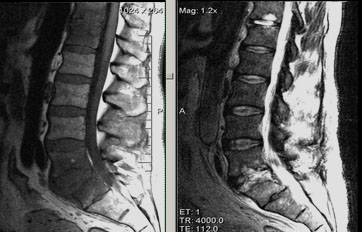

Эпидурит позвоночника на снимке КТ

Наиболее распространенные патологии при болях во время наклона вперед – эпидурит и спондилит.

Эпидурит – гнойный воспалительный процесс соединительной ткани, которая заполняет эпидуральное пространство. Заболевание может привести к поражению нервных окончаний, иногда воспаление доходит до головного мозга. При тяжелом течении образуется спинальный эпидуральный абсцесс, для лечения которого требуется оперативное вмешательство.

- в некоторых случаях для уточнения локализации и детальной картины патологии – МРТ или КТ;

- Рентгенографию (возможно, контрастную)

- При необходимости, более точное исследование при помощи КТ и МРТ